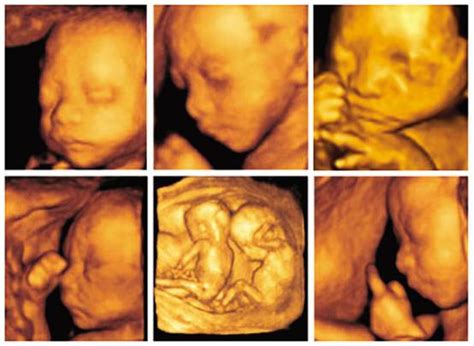

每个孕妈妈在怀孕的时候会进行产检,就像是一种检验的方式一样,达到知道宝宝的健康的快捷通道,那么在进行产检的时候怎么知道怀的是什么呢?B超显示宝宝脸朝外是男是女呢?下面的小编为大家分享B超显示宝宝脸朝外是男宝宝吗,B超孩子脸的朝向判断男女准吗大家一起来看吧。

在孕期我们都要做B超,了解宝宝在妈妈肚子里的发育情况,除了这个,B超还能看出宝宝性别,只是医院有规定,医生不能向家属泄露宝宝性别,但医院会出具做完B超后的B超单,其实B超单上是有判断宝宝性别的信息的,只是不能100%确定。